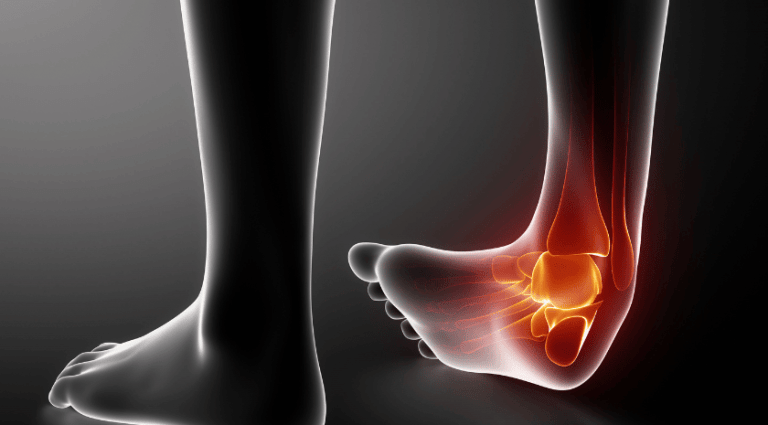

נקע בקרסול – תופעה נפוצה ביותר

נקע בקרסול הוא פציעה בפרק שהרצועה התומכת בו נמתחת או עוברת קרעים מיקרוסקופיים. מתיחה הנגרמת במעידה או "עיקום" הקרסול. האזור הופך כאוב מתנפח ומתחמם ולא ניתן לבצע בו פעולות יום יומיות.

תסמינים לנקע בקרסול

התסמינים העיקריים של נקע בקרסול, כאבים ונפיחות בצד החיצוני של הקרסול, לאחר מעידה או "עיקום" של הקרסול.